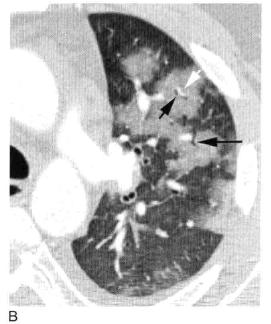

图4 实变,斑片状致密影

A.B. 支气管肺炎及小叶性实变患者增强HRCT显示单个小叶实变而周围邻近小叶正常,实变区小叶中心动脉(白箭头)和细支气管(黑箭头);C. 冠状面CT也显示斑片状实变影呈小叶性分布